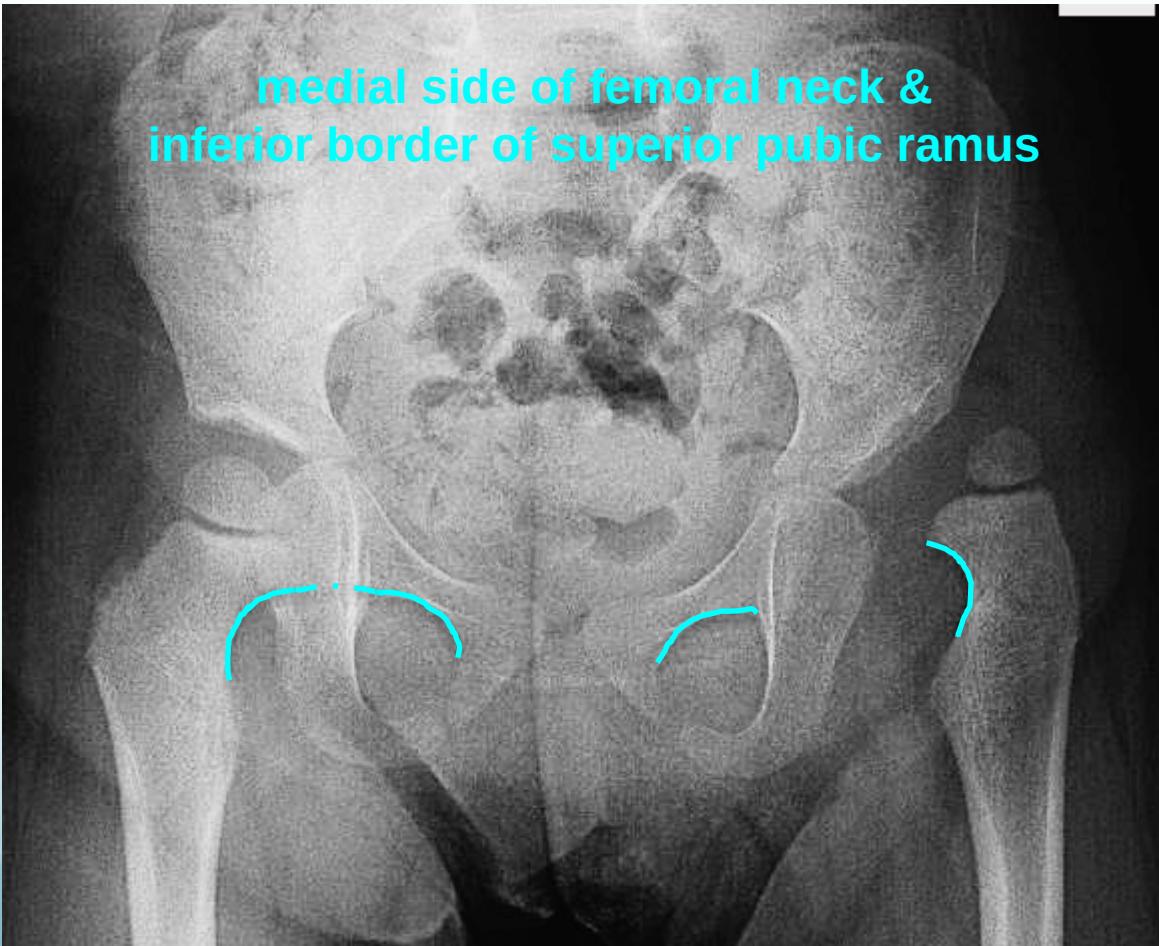

Shenton’s line: